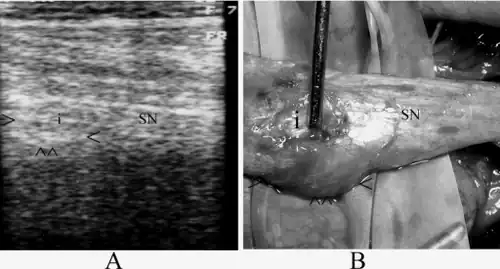

Sciatic nerve exploration can be done by endoscopy in a minimally invasive procedure to assess lesions of the nerve.[10] Endoscopic treatment for sciatic nerve entrapment has been investigated in deep gluteal syndrome. Patients were treated with sciatic nerve decompression by resection of fibrovascular scar bands, piriformis tendon release, obturator internus, or quadratus femoris or by hamstring tendon scarring.[11]